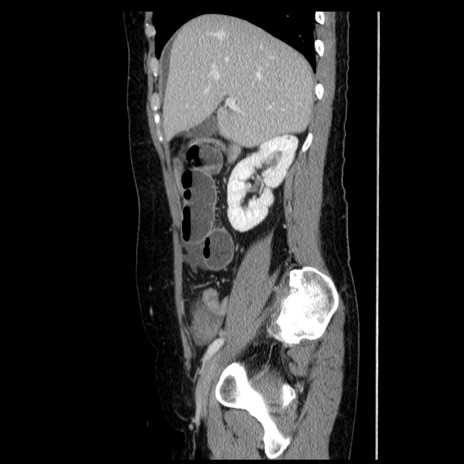

横断像

冠状断像